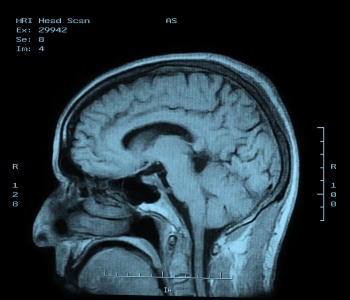

CT is one of the two technologies that utilize ionizing radiation to create a picture of what is going on inside the body. At its simplest, a CT scan is an x-ray slice of the body. Slices are repeated along the area of interest, although for performance reasons multiple slice transmitters/receivers are typically grouped next to each other. The body can also be moved during exposure in order to create a “spiral” image that can be unwound into slices or a 3D view (see Figure 1).

Figure 1: CT scan of the human brain.